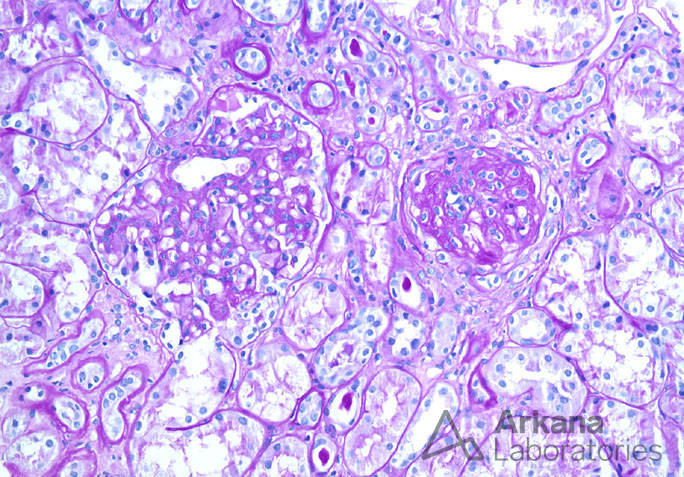

Previous Image Next Image Mesangial Expansion and Global Sclerosis in IgA Nephropathy on PAS Like Loading...